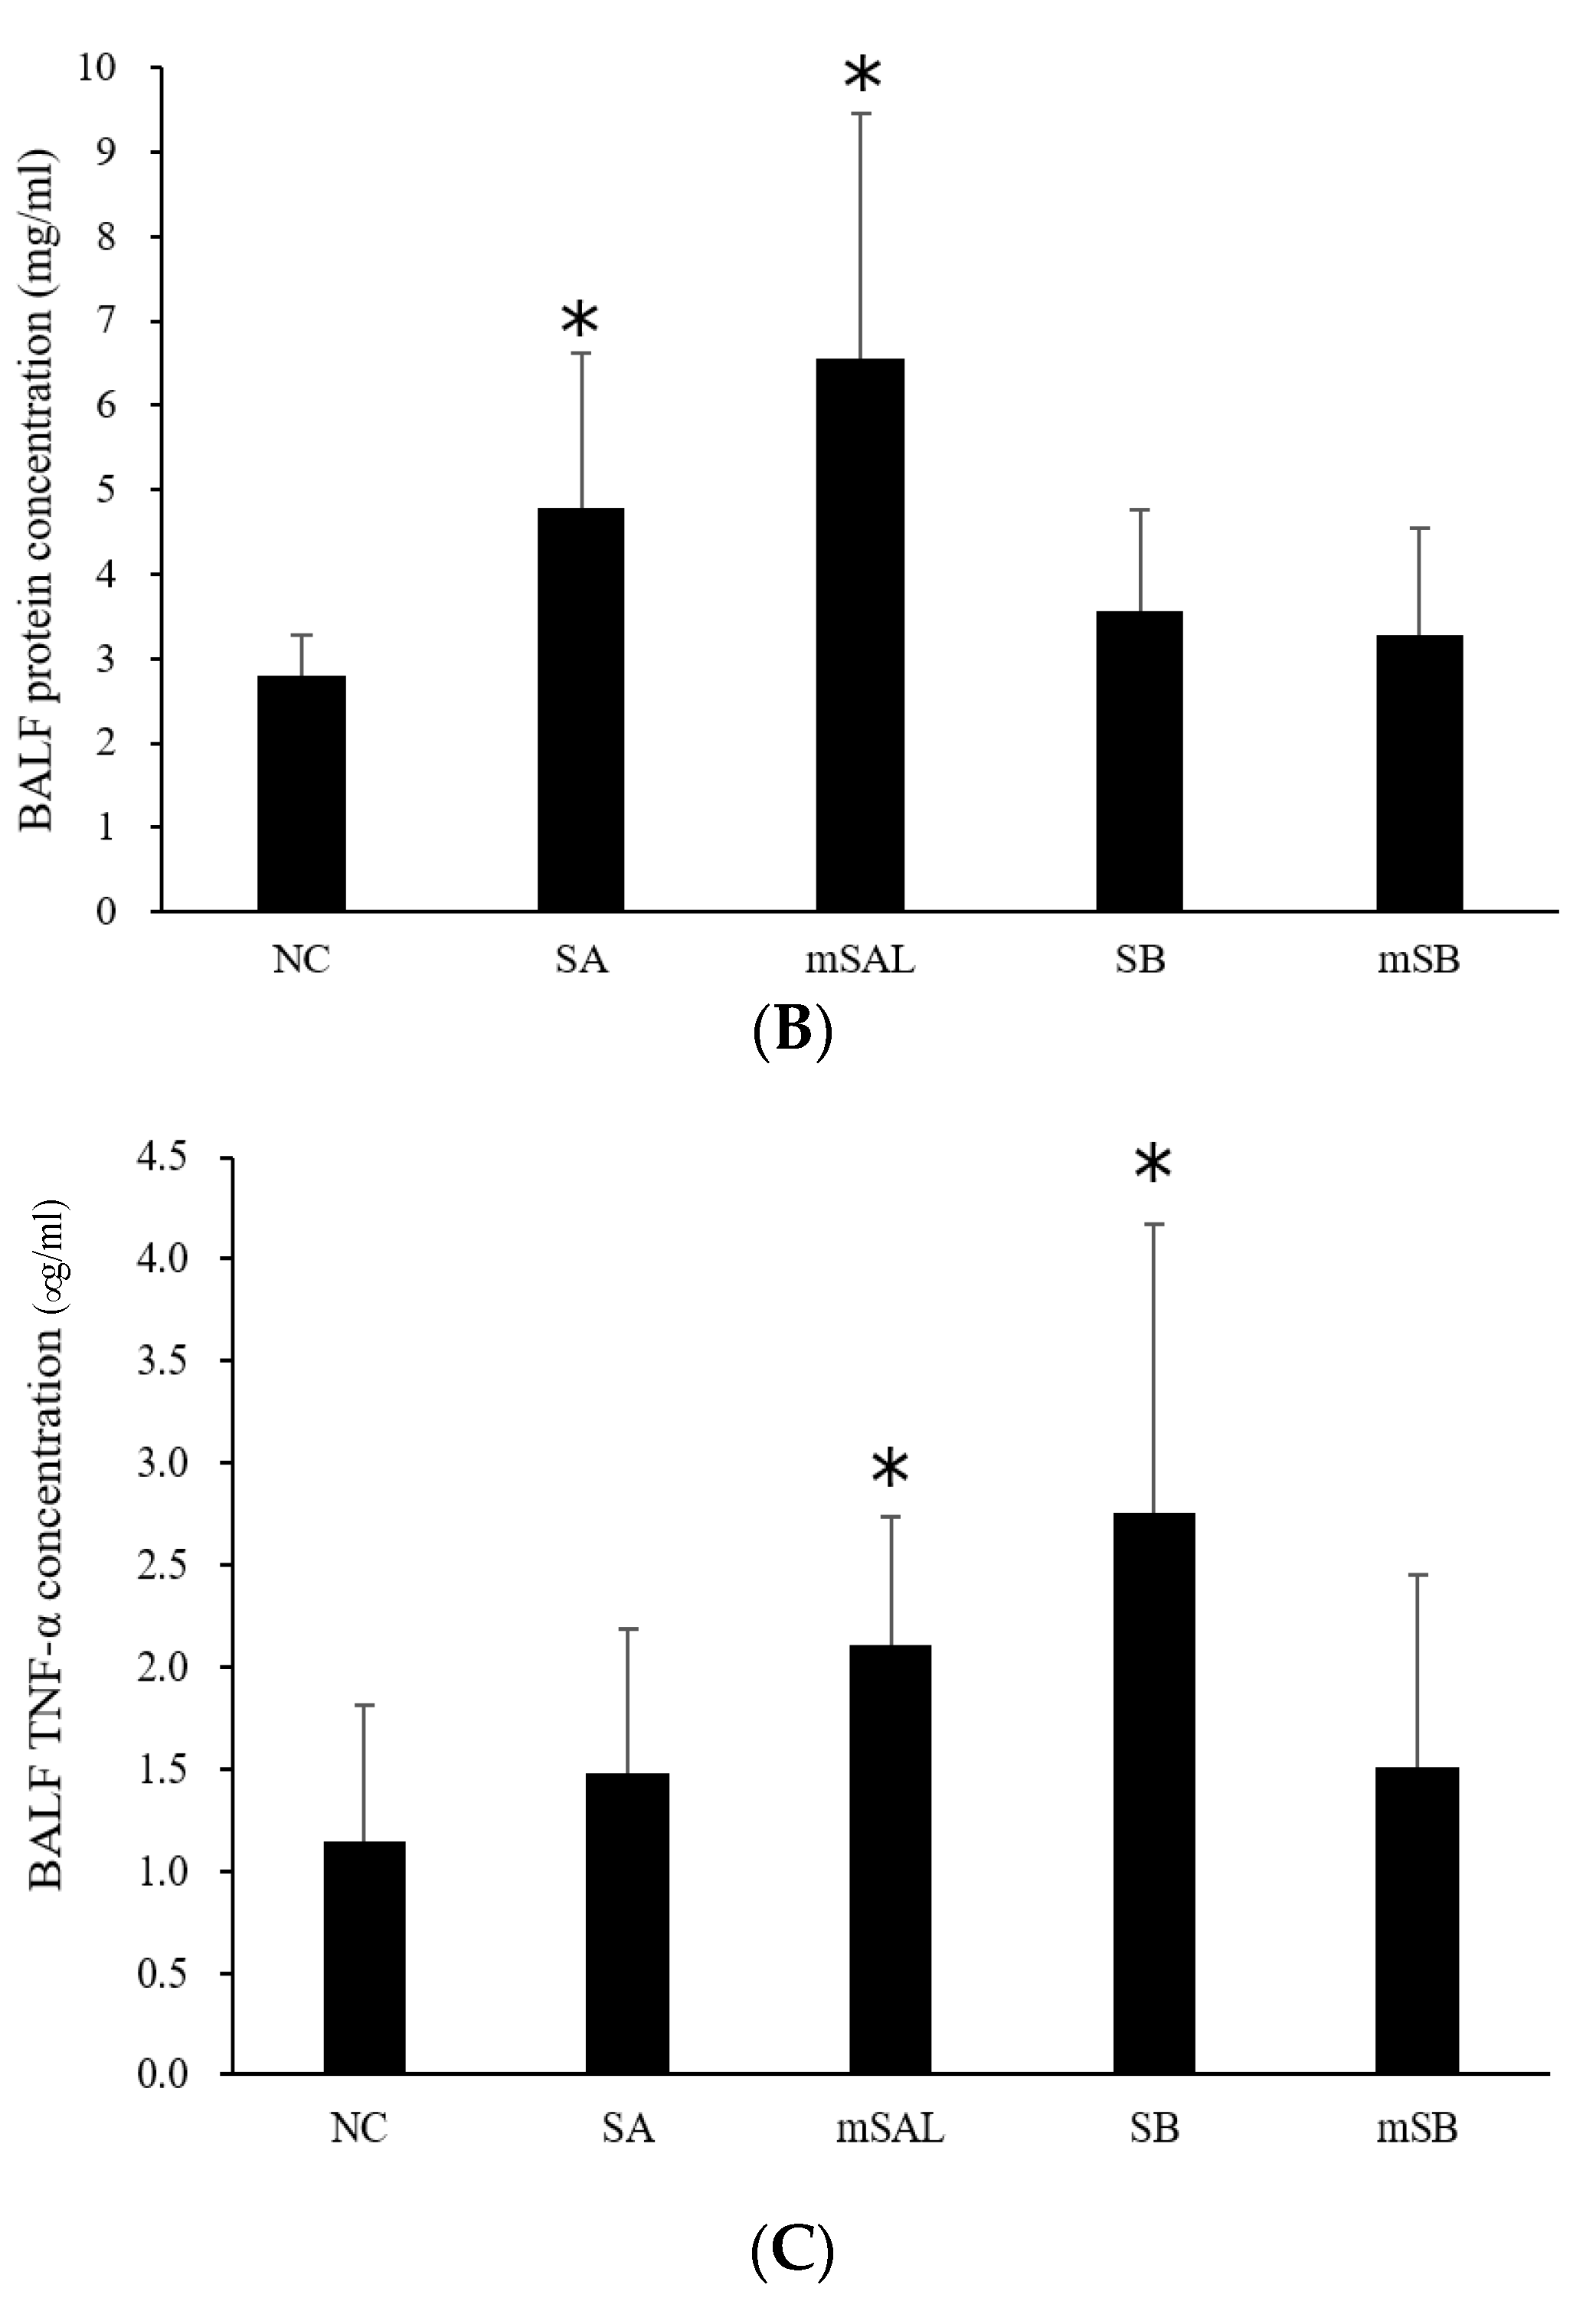

3.4. Acute Pulmonary Toxicity Test (1 D)

3.5. Acute Pulmonary Toxicity Test (14 D)

| Pathological Incidence | ||||||

| Organ | Lesions | Group | ||||

| NC 1 | SA | mSA | SB | mSB | ||

| Lung | ||||||

| Aggregate of macrophage, alveolar multifocal | - | 4/5 2 | 5/5 | 5/5 | 0/5 | |

| Granulomatous inflammation, alveolar, focal | - | - | - | 5/5 | 0/5 | |

| Pathological Scores | ||||||

| Organ | Lesions | Group | ||||

| NC | SA | mSA | SB | mSB | ||

| Lung, left lobe | ||||||

| Aggregate of macrophage, alveolar multifocal | 0.0 ± 0.0 3,4 | 2.2 ± 1.5 * | 1.6 ± 0.5 * | 2.2 ± 0.4 *,a | 0.0 ± 0.0 a | |

| Granulomatous inflammation, alveolar, focal | 0.0 ± 0.0 | 0.0 ± 0.0 | 0.0 ± 0.0 | 1.6 ± 0.5 *,a | 0.0 ± 0.0 a | |

| Total score 5 | 0.0 ± 0.0 | 2.2 ± 1.5 * | 1.6 ± 0.5 * | 3.8 ± 0.8 *,a | 0.0 ± 0.0 a | |